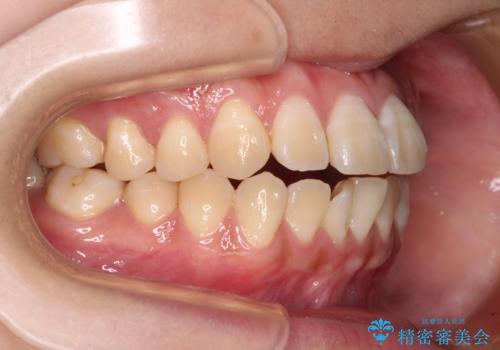

舌の突出癖による開咬と前歯の突出 インビザライン矯正治療

- 上下前歯の非接触と叢生を気にして来院された患者様です。

開咬の改善はインビザラインの最も得意とするところであるため、インビザラインを用いて矯正治療を行うこととしました。